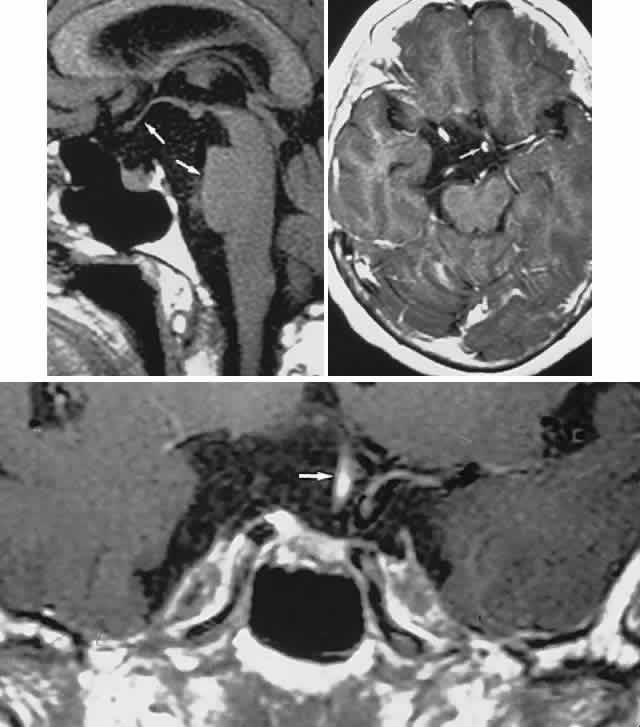

Endocrine-inactive tumors fail to produce clinical manifestations of any secretory product when a normal hormone is produced in amounts too small to be detected, when an abnormal hormone is produced but not recognized by biologic receptor sites or detected by radioimmunoassay, or when formerly endocrine-active cells have lost the ability to produce hormone as a result of degeneration. Of 1000 pituitary tumors surgically treated by Wilson,20 226 were endocrine-inactive, and 774 were secretory, as follows: PRL, 410; GH, 195; ACTH, 167; thyroid-stimulating hormone, 2. Nonsecretory adenomas, which consist mostly of null-cell adenomas, tend to be larger at presentation than do secretory tumors, with a median age of 57 years, and male predominance.21 Nonocular symptoms, as previously discussed, include chronic headaches (severe or mild) in more than two-thirds of patients,1 fatigue, impotence or amenorrhea, sexual hair change, or other signs of gonadal, thyroidal, or adrenal insufficiency. The typical sequence of hormonal deficiencies associated with large adenomas is early loss of GH and gonadotropin, later loss of thyrotropin and corticotropin. With the increasing application of neuroimaging and sensitive assays for abnormal hormones, the incidence of ophthalmologic presentation is decreasing, whereas the incidence of neuro-endocrine findings is increasing. Signs and symptoms, visual or otherwise, nonetheless may exist for months to years before so much as a visual field or plain skull film is obtained.4 Visual failure with pituitary tumors assumes a limited number of field patterns. As suprasellar extension evolves, a single optic nerve may be compromised, with resultant progressive monocular visual loss in the form of a central scotoma. More frequently, as the tumor splays apart the anterior chiasmal notch, superotemporal peripheral hemianopic defects occur. However, this well-touted superior bitemporal hemianopia is almost always accompanied by minor or major hemianopic scotomas approaching the fixational area along the vertical meridian (see Fig. 1). Asymmetry of field defects is the rule, the eye with the greater deficit likely showing diminished visual acuity. Marked asymmetry is not uncommon, such that one eye may be nearly blind while the other shows a temporal hemianopic defect (see Fig. 1C); this combination is as exquisitely localizing to the chiasm as is classic bitemporal hemianopia. Adenomas extending posteriorly produce incongruous hemianopias (see Fig. 5) by optic tract involvement; central vision is usually diminished, at least in the ipsilateral eye, and optic atrophy evolves. On extremely rare occasions, arcuate Bjerrum's scotomas extend from the blind spot into the nasal field22 or terminate at the vertical meridian.23 Such defects are usually monocular and are difficult to distinguish from glaucoma by perimetry alone. With progression, especially if the temporal field of the other eye becomes involved, a more typical field pattern evolves. In late stages of visual loss, the only suggestion of the chiasmal character of field defects may be minimal preservation of the nasal field of one eye (see Fig. 1C). The importance of serial examinations is obvious, but, when doubt exists, neuroimaging is mandatory. The absence of field defects, for example, in patients undergoing evaluation for amenorrhea, galactorrhea, or sellar enlargement incidentally discovered, does not imply the absence of an adenoma. Obviously, patients with microadenomas, that is, confined within the sella, do not have field defects. From a study24 of 50 cases of pituitary adenomas with chiasmal syndrome, it was concluded that visual disturbance occurs when the chiasm is displaced approximately 10 mm upward (see also Volume 2, Chapter 4, Fig. 6). The modern management of pituitary adenomas should involve several disciplines: current neuroradiologic studies detect microadenomas and provide precise delineation of gross morphology and status of neighboring structures, and mixed MRI signals suggest new or old hemorrhage, cysts, and so forth (Fig. 2); radioimmunoassay techniques assay PRL and other endocrine levels; oral neuropharmacologic agents, such as bromergocryptine, provide a “medical adenomectomy” for hyperprolactinemia and acromegaly; transsphenoidal surgery, including high-illumination microscopical procedures, televised radiofluoroscopic monitoring, and infection control, has all but replaced transcranial approaches; immunohistochemistry techniques have replaced the anachronistic tinctorial designations (e.g., chromophobe, basophilic) with a functional classification. PRL-secreting adenomas are the single most common type of pituitary tumor and occur more frequently in women than in men.20 Most of these tumors are microadenomas, although tumors confined to the sella are relatively rare in men. In women, amenorrhea and galactorrhea are the symptoms that provoke investigation, whereas in men, symptoms include loss of libido, impotence, gynecomastia, galactorrhea, and hypopituitarism.25 These various clinical manifestations occur with or without visual loss, depending on the volume of the adenoma; that is, the degree of suprasellar extension and compression of the chiasm. As a rule, true prolactinomas are associated with serum PRL levels higher than 150 to 200 ng/ml, and they usually range from 700 to 7000 ng/ml; the larger the tumor, the greater the serum PRL and, therefore, radiologically large adenomas with PRL levels lower than 200 ng/ml are probably nonsecreting and are not likely to respond to medical therapy (see below). Hyperprolactinemia up to 100 ng/ml may be due to simple physiologic causes, including stress, sexual intercourse, nipple stimulation, and exercise, or it may be secondary to pharmacologic agents such as phenothiazines, tricyclic antidepressants, calcium channel blockers, and cimetidine.25 However, other lesions in and around the pituitary gland and hypothalamus that compromise the pituitary stalk may present as “pseudoprolactinomas.” Immunohistochemical studies performed on 97 tissue specimens in patients operated on for presumed prolactinomas at the Mayo Clinic in Rochester, Minnesota26 revealed 65% to be microadenomas, but null-cell tumors accounted for 4 of 5 pseudoprolactinomas; these tended to be large at diagnosis, but with minor PRL elevation. Suprasellar cystic lesions can also cause hyperprolactinemia with field defects,27 as can carotid suprasellar aneurysms.28 Unlike true prolactinomas, non-PRL-secreting suprasellar tumors, with secondary hyperprolactinemia due to pituitary stalk compression, do not show a correlation between size and PRL level.29 With the advent of the ergot-derived dopamine agonist bromocriptine, there is a pharmacologic alternative (or adjunct) to surgery for prolactinomas. Bromocriptine (2-bromo-alpha-ergocryptine) is representative of a class of ergot derivatives that, since the early 1970s, have been known to inhibit pituitary gonadotropic function, reduce PRL secretion, and diminish the size of pituitary tumors (see Fig. 2). Such ergot derivatives are structurally related to dopamine, a PRL-inhibitory factor elaborated by hypothalamic dopaminergic neurons. It is likely that bromocriptine acts in two ways: dopamine turnover in tubero-infundibular neurons is depressed, thereby increasing hypothalamic dopamine; dopamine receptors of the pituitary are inhibited, reducing both spontaneous PRL secretion and the release of PRL provoked by thyrotropin-releasing hormone. At any rate, bromocriptine decreases PRL production and secretion, with resultant reduction in lactotrope size and subsequent diminution of tumor volume, often rapidly, within 1 to 2 hours of initiation of treatment.25 Spark and associates,30 among others, reported the efficacy of bromocriptine in reducing tumor size; it was demonstrated that bromocriptine lowered PRL, reduced GH in acromegaly, and reversed visual field defects. However, patients with extrasellar extension or with high PRL levels did less well. The great weight of evidence now clearly shows that most microadenomas (intrasellar) are demonstrably reduced in size,31 in about 3 months at an average dose of 5 mg per day, but cystic necrosis may develop, and adenomas may increase in volume if bromocriptine is discontinued. The tumor-reducing effect of bromocriptine on prolactinomas has been tested on 5 types of large, extrasellar pituitary tumors.32 Twenty patients were treated prospectively for up to 4.5 years with bromocriptine 30 mg or 60 mg per day (2 patients received 15 mg and 160 mg, respectively), and the effect on the size of the pituitary tumors was quantitated by planimetry of CT scans before and during treatment. The immediate success rate was 16 of 20 tumors, and 11 nonsecreting tumors were reduced by a median of 32%, with an immediate success rate of 9 of 11. Nine secreting tumors (4 that secreted PRL; 3, GH; 1, ACTH; and 1, thyroid-stimulating hormone) were reduced by a median of 51%. The reduction in tumor size was significantly associated with pretreatment volume, but not with the hormonal serum concentrations or with previous radiation treatment. Moreover, bromocriptine treatment did not cause any pituitary insufficiency other than the desired suppression of PRL. The clinical course of 10 patients with macroprolactinomas at the Wills Eye Hospital in Philadelphia was carefully documented33 after treatment with bromocriptine in daily doses ranging from 7.5 to 30 mg. Nine patients enjoyed improvement in acuity and fields quite rapidly, often within a few days, including the following: hand movements to 20/20 within 1 month, counting fingers to 20/20 or 20/30 within 7 to 12 days, and dramatic recovery of field defects. There was also a demonstrable decrease in tumor size by CT criteria, and lowering of serum PRL. Four patients subsequently required transsphenoidal decompression, for conditions including failure of visual improvement, cerebrospinal fluid (CSF) rhinorrhea, and medication intolerance. The authors cautioned that the long-term effects of bromocriptine therapy are not known, and prompt tumor regrowth is to be anticipated when the drug is discontinued. It was recommended that patients who are to undergo surgical decompression should be treated preoperatively to decrease tumor size and “to facilitate surgical removal,” and that residual tumor with elevated PRL should be treated with bromocriptine. A similar patient34 with a large pituitary tumor, hyperprolactinemia, bitemporal fields defects, and invasion of one cavernous sinus (involving the fifth and sixth cranial nerves) was treated with bromocriptine 7.5 mg per day,35 with marked reduction in the tumor size and resolution of field defects and cranial nerve dysfunction over a 6-month period, at which point the sella appeared empty. Other dopamine agonists are available or under investigation, including long-acting bromocriptine (Parlodel), cabergoline, and CV-205-502; some prolactinomas resistant to standard dopamine agonists may respond to more potent agents such as cabergoline.35 Ophthalmic results in patients with macroprolactinomas treated with dopamine agonists show generally good results, with few instances of pituitary necrosis.25,36 Indeed, it may be that these newer pharmaceuticals should be the treatment of choice in patients with large pituitary tumors with extrasellar extensions. These unquestionable successes notwithstanding, there remain unanswered questions concerning dopamine agonist therapy: Is long-term medical therapy preferable to simple transsphenoidal surgery? Can such patients ever be weaned from medical therapy? What about the ultimate outcome of tumors not characterized by PRL secretion? Should large, asymmetric (invasive?) adenomas be pretreated to make surgical removal easier? Based on an extensive experience, Wilson20 recommended microsurgical transsphenoidal removal of macroprolactinomas, with presurgical bromocriptine treatment of tumors larger than 2 cm. The details of neurosurgical procedures are beyond the scope of this present work, but Wilson's review and other sources37 should be consulted. Varying within the spectrum of surgical experiences, complications of transsphenoidal procedures include anterior pituitary insufficiency (about 20%), diabetes insipidus (about 18%), CSF rhinorrhea (about 4%), and, rarely, loss of vision or diplopia.38 Infrequent untoward results include hydrocephalus secondary to subarachnoid blood, cerebral ischemia related to vasospasm, meningitis with or without CSF leak, and death associated with intraoperative or postoperative hemorrhage.20,38 Radiation therapy is currently used as an integral part of postoperative treatment in patients with incompletely resected nonfunctional adenomas. External-beam conventional protocols delivering median total dosage of 45 Gy are considered highly effective in preventing recurrence of hormonally inactive tumors, but they may compound relative hypopituitarism.39 Young patients with total tumor removal, or without MRI evidence of recurrence, may be safely observed with radiation therapy held in reserve. The role of stereotactic radiosurgery (single-fraction high-dosage) of pituitary adenomas is not yet clear, preliminary results notwithstanding.40 Following uncomplicated surgical decompression, visual acuity and fields may return with dramatic speed or improve weekly. Such restoration is dependent on duration of visual morbidity and, to some extent, the degree of pallor of the optic discs. Preoperatively, if careful ophthalmoscopy reveals attrition of the retinal nerve fiber layer, corresponding field defects are permanent. For the most part, what vision returns does so by 3 to 4 months, if not sooner, but many months may pass before maximum recovery is attained. Not all surgical procedures are successful, and visual function may worsen, especially after frontal craniotomy for large adenomas with massive suprasellar extension. Visual deterioration at or immediately following surgery is related to intrasellar hematoma formation, edema of tumor remnants, or direct surgical manipulation of optic nerves or chiasm and adjacent vasculature. Arterial injuries, for example, 21 instances in more than 1800 cases, produce intraoperative hemorrhage, delayed epistaxis, carotid arterial occlusion, and pseudoaneurysm.41 Postoperative packing of the sella with muscle or subcutaneous fat may compress the optic nerves and chiasm, for which reason MRI is warranted when vision is worsened or does not recover quickly within a few days.42 After surgical, medical, or radiation therapy, the visual fields should be assessed as soon as possible to determine baseline function. In uncomplicated cases, monthly intervals during the first 3 months should suffice, then at 6 months, and subsequently yearly follow-up are usually adequate. Recurrence of visual failure may be caused by regrowth of tumor, arachnoidal adhesions associated with a progressive “empty sella syndrome” (see below), or delayed radionecrosis (see below). Tumor recurrence is by far the most common mechanism of visual deterioration, but field examination alone may not make this distinction. With prolactinomas, serum PRL levels may be monitored, and, indeed, prolactinomas have a higher recurrence rate than nonsecreting tumors.43 Although it is not known for certain which factors influence risk of recurrence, certainly the original size of the tumor does, as well as PRL activity. In one series,44 the rate of recurrence in 56 patients with large adenomas, all but 1 having received postoperative irradiation, was 20% (11/56), occurring between 6 months and 6 years. Again, it was not clear that original tumor size was related to more aggressive growth or high recurrence rate, but no histologic differences were found between tumors that were large and relapsing and those that were smaller and did not recur. In another series45 of 100 nonfunctioning pituitary tumors, of which 82% were null-cell adenomas, symptomatic recurrence developed in 6 patients, and 10 demonstrated radiographic recurrence during 48 to 100 months (mean, 73.4 months) of observation after transsphenoidal surgery; the effect of radiation therapy was moot. The follow-up of treated adenomas has been problematic, from the standpoint of detecting recurrence. As adenomas must be large initially to cause visual defects, so must recurrences be substantial before defects again evolve. Although progressive visual failure may be the incontestable impetus for re-operation or irradiation, consecutive perimetry may not be counted on to reveal “early” tumor recurrence. An anatomic assessment, as provided by CT scanning or MRI with coronal views, provides the most sensitive technique for monitoring tumor regrowth. In addition, measurement of serum PRL levels in the immediate postoperative period and at regular intervals is a rational way to determine recurrence of prolactinomas. Pituitary adenomas may act more aggressively on occasion, invading the laterally adjacent cavernous sinuses and producing acute or chronic cranial nerve palsies (see Volume 2, Chapter 12). Potential markers for aggressive biologic behavior include p53, MIB-1, PCNA, RB, and H-ras; a high MIB-1 antibody index indicates active proliferation, as does positive p53.46 Indeed, prolactinomas may metastasize. A case of “sinusoidal adenoma” invading the skull base, pterygoid, and orbit of a 12-year-old boy was reported47; the cytologic picture suggested “a higher degree of malignancy than usual,” but it did not appear to be an undifferentiated carcinoma. Another rare instance of an invasive pituitary adenoma was described also in a 12-year-old boy who presented with severe headache, vomiting, rapid loss of monocular acuity, and sixth nerve palsy48; histologically, there was absence of cellular pleomorphism or of mitosis despite the invasive course. Histologic criteria apparently are not sufficient to indicate invasive tendencies, and local extension is not evidence of malignancy. Seeding of the subarachnoid space and spread outside the cranium are extremely rare complications that indicate biologic malignancy. Malignant lesions of the pituitary may be initially mistaken for simple adenomas, including sellar plasmacytoma, lung, and breast metastases49; atypical features suggesting malignancy include rapidly progressive visual loss, ocular motor palsies, and facial numbness (see also below, Metastatic Diseases and Other Mass Lesions). In addition, benign and rare vascular malformations of the sella fossa are reported.50 ACROMEGALY Other adenomas secrete ACTH or thyroid-stimulating hormone or are “mixed” (most commonly PRL- and GH-secreting), but they are principally of endocrinologic interest and relate to neuro-ophthalmology only when extrasellar extension produces field defects. However, acromegaly requires further elaboration. Acromegaly is the clinical condition associated with excess GH either from autonomous pituitary adenoma secretion or from hypothalamic production of GH-releasing factor with subsequent GH hypersecretion. Many GH-secreting tumors contain a mutant form of the chain of GS protein in the somatotrope. This represents a relatively rare endocrinopathy, although in Wilson's surgical series20 of 1000 transssphenoidal procedures, there were 195 cases of GH-secreting adenomas, and 228 cases of acromegaly were found among 1000 adenomas seen at the Mayo Clinic from 1935 to 1972.51 Clinical features include bone and soft tissue enlargement, especially of hands, feet, and face, visceromegaly, arthritis and carpal tunnel syndrome, hypertension, diabetes, hyperhidrosis, weakness, arthralgias, tooth malocclusion, headaches, impotence, menstrual irregularities, and abnormal glucose tolerance test results. Adenomas associated with acromegaly seem not to expand beyond the sella with the regularity typical of prolactinomas or nonsecretory tumors. This phenomenon may be attributable to earlier detection as a consequence of prominent clinical manifestations. Nonetheless, 144 of 228 patients with acromegaly in the Mayo Clinic series51 had visual field defects, a finding that may reflect delay in diagnosis in a series commenced 6 decades ago. The use of octreotide and other long-acting analogs of somatostatin are indicated as follows: for the treatment of patients with active disease when surgery or radiation therapy has failed or is contraindicated; while awaiting the clinical effects of radiation therapy; as primary treatment in the elderly and medically incapacitated.52 Long-term octreotide therapy reduces serum levels of GH and insulin-like growth factor-1, and it reduces tumor size.53 Ablation of GH-adenomas is also achieved with various forms of radiation therapy, but more or less immediate remission is best accomplished by transsphenoidal resection. PITUITARY “APOPLEXY” Pituitary “apoplexy” refers to an acute change in volume of a pituitary adenoma as a result of spontaneous hemorrhage, edematous swelling, or necrosis. Postpartum infarction or hemorrhage in nontumorous glands does occur, as firmly established in the obstetric literature as “Sheehan's syndrome,”54 but chiasmal compression is a rare event. Even in clinically silent cases, adenoma necrosis with cystic liquefaction and evidence of previous bleeding is encountered commonly enough and may be identified by radiologic criteria (see below). Gross or microscopic hemorrhagic necrosis is apparently independent of endocrine activity or neoplastic pattern. In a review55 of 320 verified adenomas, with a high incidence in giant or recurrent large adenomas (41%), evidence of hemorrhage was found in 58 cases (18%). Mean age was 50 years, and clinical courses included the following: acute apoplexy, 7 cases; subacute apoplexy, 11 cases; recent silent hemorrhages, 13 cases; old silent hemorrhage, 27 cases. That is, in 58 cases of hemorrhage in adenomas, 40 were symptomatically silent. From a series56 of 453 operated adenomas, 45 (10%) demonstrated hemorrhage, but only 13 of these patients had acute symptoms of pituitary apoplexy; the authors correlated hemorrhage with marked suprasellar extension. Wilson20 concluded that most massive pituitary tumors are prolactinomas, and there is “evidence of necrosis in most prolactinomas”; spontaneous necrosis or hemorrhage is related to indolent tumor growth; that is, tumor cell population expands or contracts at a rate determined by the balance of cell production and cell death. Hemorrhage into adenomas is documented following head trauma,57 after cardiopulmonary bypass,58 and subsequent to tests of pituitary function using thyroid-releasing hormone, gonadotropin-releasing hormone, and insulin.59 Additionally, uncomplicated pregnancy, bleeding disorders, radiation therapy, adrenalectomy, and physical exertion are all reported predisposing factors in pituitary “apoplexy.”60 Indeed, pituitary hemorrhage may occur in adolescence,61 principally in prolactinomas. Clinical signs and symptoms include the following: acute onset of severe headache, often sickening frontal or retro-bulbar cephalgia, or other less disabling change in headache pattern; acute or rapidly progressing unilateral or bilateral (usually asymmetric) ophthalmoplegia due to rapid expansion into cavernous sinuses (see also Volume 2, Chapter 12); epistaxis or CSF rhinorrhea when the mass ruptures or erodes into the sphenoid sinus; complications of blood or necrosis debris in the CSF, with “pseudomeningitis”; rapid neurologic deterioration and obtundation, although patients need not be stuporous; and, greater or lesser degrees of hypopituitarism.62,63 Selective expansion laterally into the cavernous sinus may produce ophthalmoplegia without visual loss; selective expansion superiorly may produce visual loss without ophthalmoplegia. Almost without exception, enlargement of the sella is found even on plain skull film views; both CT and MRI detect fresh hemorrhage (Fig. 3), but MRI may fail to demonstrate acute hemorrhage unless specific sequences are employed (hemorrhage may be isointense on T1-weighted images and hypointense on T2-weighted images; in the subacute phase, extracellular methemoglobin should appear bright on both T1 and T2 sequences). Corticosteroid replacement and other supportive measures may be critical, and, in most instances, decompression through the sphenoid sinus is advisable, sooner rather than later. Bromocriptine has been suggested as a temporizing measure when signs and symptoms are modest and not progressing,64 and there are advocates65 for conservative management consisting of intravenous dexamethasone, so long as visual deficits are minimal or rapidly improve; otherwise decompressive surgery is required. Given the regularity with which pituitary apoplexy is often a delayed diagnosis, being confused with ruptured aneurysm or meningitis, for example, and that transsphenoidal surgery is a relatively simple undertaking, further procrastination in decompression of the compromised visual pathways is to be avoided. Imaging of Pituitary Tumors In addition to the radiologic implications mentioned previously, specific points should be emphasized. Contrast-enhanced CT and, especially, MRI have replaced all previous radiologic techniques in the detection and anatomic assessment of sellar and juxtasellar lesions. MRI has also the inherent advantage of using no radiation, nor does it require iodinated contrast injections. Although thin-section contrasted CT does indeed disclose most lesions, bone changes, and recent hemorrhage, MRI is superior in delineating distortions of optic nerves and chiasm, in displaying arteries, and in revealing fat, hemorrhage, or cyst (see Figs. 3E through M). Indeed, in a prospective study of normal volunteers, gadolinium-enhanced MRI disclosed pituitary adenomas (3 mm to 6 mm in diameter, i.e., microadenomas) in 10% of adults aged 18 to 60 years.66 T2-weighted fast spin-echo MRIs are currently the most precise sequence for demonstrating the optic nerves and chiasm, even when these structures are severely distorted by suprasellar tumor extension.67 The question of invasion or displacement of the cavernous sinus has been studied by MRI technique,68 with the following conclusions: the normal cavernous sinuses are usually symmetric but vary in size; the lateral dural margins are easily recognized as linear, discrete, low-intensity structures; the medial dural margin (pituitary capsule) is rarely discernible; sensitivity of predicting cavernous sinus invasion is only 55%; no features permit certain distinction between invasive and noninvasive adenomas, because the medial wall of the cavernous sinus is not reliably identified; the most specific sign of invasion is carotid artery encasement. Normal pituitary glands extend laterally into the cavernous sinus in 29% of microanatomic dissection specimens.69 A study70 of the CT appearance of pituitary masses after transsphenoidal surgery showed that the superior limits do not return to normal immediately despite complete tumor removal, but only gradually regress in 3 to 4 months. This phenomenon is variably due to blood clot in the sella, to muscle or fat used as packing material, and to adhesions between the diaphragma sellae or tumor and brain tissue above. Therefore, neuroimaging in the immediate postoperative period may be misleading, and baseline radiologic evaluation may be delayed for 3 to 4 months, unless otherwise indicated. MENINGIOMAS Posterior perioptic foraminal, medial sphenoid ridge, and tuberculum sellae meningiomas produce prechiasmal (optic nerve) or chiasmal compression, as do olfactory groove and planum masses that extend posteriorly. Visual deficits usually take the form of slowly progressive monocular loss of vision, and, when both fields are involved, there is a distinct tendency toward marked assymetry, frequently with extensive visual deficit on one side before the contralateral field becomes involved. Slow growth across the tuberculum eventuates in contralateral optic nerve or chiasmal interference. There is a distinct predilection for meningiomas to occur in middle-aged women, and enlargement during pregnancy, as well as possible association with breast cancer, supports evidence for the role of estrogen and progesterone receptors.71 Although nonspecific headaches are a common feature of suprasellar meningiomas, most patients present with monosymptomatic failure of vision and are thus likely to present initially to the ophthalmologist. Although relentless deterioration of vision is the rule, fluctuations over weeks or months may mimic optic neuritis.72 Slavin73 documented an exceptional case of acute, bilateral central scotomas developing over 2 weeks, in the presence of a gigantic meningioma that extended into the ethmoid sinuses and under the frontal lobes. In a series of suprasellar meningiomas,74 the time interval from the onset of unilateral visual loss to subjective bilateral defects, was 1 to 8 years; simultaneous bilateral onset was not documented. Although periocular pain made worse by eye movement is typical of inflammatory optic neuritis, Ehlers and Malmros75 reported this symptom with suprasellar meningiomas. Asymmetric optic disc pallor is a relatively “late sign,” normal discs being fully compatible with visual loss over many months. The much-touted Foster Kennedy syndrome, that is, optic atrophy with contralateral papilledema due to large subfrontal meningiomas, remains a distinct rarity.75 Anosmia, also classically considered an important finding with olfactory meningiomas, is much overrated and is difficult to assess. Delayed diagnosis of large tumors results in frontal lobe compression and edema causing mental changes or hydrocephalus due to obstruction of the ventricular system. In previous decades, chiasmal interference with optic atrophy, but “normal” plain skull films, was referred to as “Cushing's syndrome of the chiasm,” caused by meningiomas, aneurysms, or other noncalcified suprasellar lesions. The modern neuroimaging techniques of enhanced CT, “bone-window” protocols, and gadolinium-contrasted MRI are now exceedingly sensitive in disclosing meningiomas or other parachiasmal masses (Fig. 4). At present, contrast-enhanced CT or MRI precisely demonstrate extra-axial tumor configuration; CT is superior in disclosing calcification or bone changes, but it is inferior for assessing suprasellar or intrasellar extension, postsurgical changes, and vascular displacement or encasement.76 Whether MRI or even MR angiography obviates standard selective arteriography, especially when surgical intervention is contemplated, is moot. In a large surgical series,77 257 patients underwent 338 craniotomies for meningiomas at diverse intracranial locations. Of these, there were 35 sphenoid wing, 20 olfactory groove, 12 tuberculum sellae, and 2 orbito-cranial meningiomas; that is, about 27% of tumors were of potential neuro-ophthalmologic interest. For the entire series, average observed survival was 9 years, and recurrence rate was 22% overall. At the Massachusetts General Hospital in Boston,78 of 225 patients operated on for meningioma, parasellar tumors constituted 12%; only half of these were considered grossly “completely excised,” but with a 5-year probability of recurrence or progression of 19%. No radiation therapy was applied in this series. Rosenberg and Miller79 analyzed the visual results in 16 patients following modern microsurgical removal of meningiomas involving the intracranial optic nerves or chiasm. Median age at diagnosis was 56.5 years, and median duration of visual symptoms was 19.5 months. Visual acuity improved in 12 of 32 eyes, worsened in 8 (3 optic nerves were transected; 5 eyes showed an average drop of 2.6 lines in acuity), and 10 eyes retained normal function. Visual outcome appeared to be related most closely to duration of symptoms. The response of meningiomas to irradiation has not been clearly established. In general, growth and regrowth rates are extremely slow, compounding the problem of assessing the question of radiotherapeutic efficacy. In a series of 12 incompletely resected meningiomas (8 sphenoidal, 2 petrosal, 1 each orbital and parasagittal), patients were subjected to 4800 to 6080 cGy (median dose, 5490 cGy) in 6 weeks80; median postradiation follow-up was 54.5 months (range, 20 to 120 months), and 9 patients were said to remain free of clinical or radiologic signs of tumor progression. Recurrent lesions were discovered at 4, 6, and 9 years, and the authors concluded that postoperative radiation therapy is indicated for incompletely excised meningiomas. Carella and colleagues81 reviewed the experience with 68 patients, 49 women and 19 men, divided into 3 groups: (A) 43 patients who had surgery (42 with known residual tumor) followed by irradiation; (B) 14 patients who had radiation for recurrence, of whom 11 underwent subtotal resection before radiation therapy; (C) 11 patients who had radiation as primary treatment. In Group A, 41 of 43 patients were alive, most doing well neurologically after 1 to 10 years; in Group B, 5 were dead of meningioma (all within 3 years), and 7 patients were considered “stable”; in Group C, all were alive at 3 to 6 years, 9 with neurologic improvement, and 4 with CT evidence of tumor shrinkage with central necrosis. Conventional fractionated radiation therapy continues to provide mixed results,82,83 and stereotactic radiation therapy with single-fraction dosage has enthusiastic advocates, but relatively short-term follow-up data.84 Undoubtedly, external-beam radiation therapy has a role as an effective adjunctive treatment in the control of meningioma recurrence, but the possibility of collateral damage, including radionecrosis (see below) of vital neural structures, must be considered. With reference specifically to results of radiation therapy of meningiomas involving the anterior visual pathway, Kupersmith and coworkers85 analyzed 4 patients treated by irradiation alone and 16 treated in combination with tumor excision. Improvement in visual function occurred in 13 patients, 2 showed temporary improvement, and 5 maintained stable function for up to 9.5 years; follow-up CT did not disclose reduction in tumor size. The study by Kennerdell and associates,86 dealing primarily with optic nerve sheath meningiomas, inferred a distinct salutary effect of irradiation alone or as a supplement to partial microsurgical resection. The management of menigiomas involving the intracranial optic nerves and chiasm may be summarized as follows: surgery remains the principal initial endeavor, in some instances with efforts intended only at judicious gross “debulking”; postoperative radiation therapy at least appears to increase the recurrence-free interval in cases of incompletely resected tumors; radiation therapy alone (dosage range, 5000 to 5500 cGy) is an acceptable alternative in patients considered poor surgical risks, especially where tumor has encased major arteries or invaded the skull base or when neuroimaging demonstrates surgically inaccessable optic nerves or chiasm. Complications arise when adhesions of tumor to portions of nerves or chiasm, or to vessels, are agressively manipulated in attempts at “complete removal.” Progesterone receptor sites are expressed in 81% of women and 40% of men with meningiomas,71,84 with 96% of benign and 40% of malignant meningiomas containing progesterone receptor-positive nuclei, but without correlation between progesterone receptor index and age or histologic subtype.71 Moreover, the efficacy of antiprogesterone agents such as mifepristone has proved disappointing.87 At present, immunotherapy in the form of interferon-alpha is under investigation.88 Treatment options, or the absence thereof, must be considered in light of the glacial growth rate of most meningiomas. For example, Olivero and colleagues89 found that 78% of 60 asymptomatic meningiomas followed for over 2.5 years demonstrated no growth, and the remaining 22% showed a mean growth rate of only 0.24 cm in maximum diameter per year. Therefore, judicious observation may prove the best option, especially in the elderly or in patients with considerable risk for surgical intervention. Recurrence or regrowth of tumor is best monitored by contrast-enhanced CT and gadolinium-enhanced MRI. After initial postoperative baseline visual field plotting, consecutive perimetry discloses visual failure only as a relatively late sign of tumor enlargement. Perioptic meningioma of the intraorbital portion of the optic nerve is considered in Volume 2, Chapter 5, Part II. CRANIOPHARYNGIOMAS Craniopharyngiomas are tumors that arise from vestigial epidermoid remnants of Rathke's pouch, scattered as cell rests in the infundibulo-hypophyseal region. These tumors are usually admixtures of solid cellular components and variable-sized cysts containing oily composites of degenerated blood and desquamated epithelium or necrotic tissue (and blood) with cholesterol crystals. Dystrophic calcification of this debris is detectable with plain films and CT imaging and is an important radiologic sign estimated to be seen in more than 80% of childhood craniopharyngiomas. These tumors are congenital (dysontogenic) and, in rare instances, may present in the neonate. There is a more or less bimodal age incidence, peaking in the first 2 decades and again in the years 50 to 70 (Fig. 5). These predominantly suprasellar tumors account for 2% to 4% of all intracranial tumors regardless of age group, but the incidence is 8% to 13% in children. Of all suprasellar masses, craniopharyngiomas comprise 54% in children, and 20% in adults, and show two clinicopathologic and pathogenetic separate types: adamantinous (predominantly cystic, in childhood) and squamous-papillary (predominantly solid, adulthood).90 Presentation in childhood is commonly related to hydrocephalus and endocrinopathies, consisting of variable degrees of hypopituitarism with or without diabetes insipidus; obesity and somnolence also attest to hypothalamic disturbance. Gonadotropic hormone deficit results in retarded or absent sexual development, and precocious puberty is rare. In children, progressive visual loss goes unnoticed until a level of severe bilateral impairment is reached, or unless headache, vomiting, and behavioral changes occur. Increased intracranial pressure produces papilledema in about 65%, and optic atrophy is observed in roughly 60%.91 In adults, visual deterioration is the universal symptom that demands investigation, although occult endocrine dysfunction may be uncovered; hypopituitarism, diabetes insipidus, amenorrhea, and galactorrhea inconstantly eventuate. Visual field defects are frequently asymmetric bitemporal hemianopias or a homonymous pattern with reduced acuity (Fig. 6) when the optic tract is compressed.92 CT scanning retains special relevance to craniopharyngioma diagnosis, currently superior to MRI in detection of calcification and cyst formation (Fig. 7A to C); however, the extent of involvement of adjacent structures, that is, the optic chiasm, third ventricle, and intracavernous carotid artery, is more clearly delineated by MRI (Fig. 7D and E).93 Craniopharyngioma fluid collections are found to be uniformly bright on T2-weighted sequences, but on T1-weighted images, the signal intensity may range from hypointense to hyperintense, reflecting the heterogeneous contents of cysts. Because calcification and cyst formation are hallmarks of craniopharyngiomas, CT is more specific than MRI. At times, intrinsic infiltration of tumor may thicken the chiasm and contiguous optic nerve, a radiologic configuration that mimics glioma.94 Likewise, glioma may be simulated when the optic canal is invaded and enlarged, but accompanying bony erosion of the sella weighs heavily toward craniopharyngioma. More than half a century ago, Harvey Cushing declared that craniopharyngiomas “offer one of the most baffling of surgical problems,” and were “disheartening from an operative standpoint.”95 Fortunately, in the modern era, the surgical microscope, steroid replacement, radiation therapy, and valve-regulated shunts have all proved valuable adjuncts to the operative management of these masses. Since the time of Matson, a major neurosurgical school of thought was preoccupied with “complete” removal of craniopharyngiomas in preference to subtotal extirpation. Although primary total removal is no doubt ideal, this is actually only rarely accomplished. The question of “matsonian total removal” was addressed in the 1975 follow-up by Katz,96 who analyzed the results of surgical management in 51 of Matson's patients operated upon between 1950 to 1968; there was a 25% operative mortality, a 71% 11-year mortality, and 76% of those cases examined by autopsy had residual tumor at the time of death. A less ambitious approach consists of cyst aspiration, intracapsular dissection, cyst drainage via subcutaneous reservoir, and radiation therapy. In a series of 43 children at the Columbia-Presbyterian Medical Center in New York from 1952 to 1977,97 10-year actuarial survival rates were 52% for subtotal resection alone and 87% for subtotal plus radiation (mean, 5000 cGy). Tumors had recurred by 10 years in half of 14 children in whom removal was thought to be total, in more than 90% of those whose tumors were subtotally removed, and in less than 25% of those at risk after subtotal resection and irradiation. Recurrences were usually evident within 2 years, but more delayed after “total” resections. From a later series of 37 children cared for at Children's Hospital, Boston, from 1972 to 1981,98 it was concluded that radiation therapy was equally, if not more, effective than attempted excision in controlling subsequent tumor growth. It is inferred that conservative surgery combined with irradiation (mean dose, 5464 cGy) offers less risk for psychosocial impairment than does tumor excision, although the delayed effects of radiation to the juvenile brain must be taken into account (see the discussion of therapy for optic glioma, below). Craniopharyngiomas that arise low on the hypophyseal stalk are subdiaphragmatic and may be approached via the transsphenoidal route99; cystic recurrences may also be managed by transsphenoidal drainage, although surgical cure is unlikely. Interestingly enough, the first craniopharyngioma operated on successfully was reported in 1910, by Halstead, via the transsphenoidal approach.100 Regardless of surgical approach or use of radiation therapy, endocrine replacement is anticipated in all cases, often for life. OPTIC AND HYPOTHALAMIC GLIOMAS As noted in Volume 2, Chapter 5, Part I, astrocytic tumors of the anterior visual pathways present as two unrelated pathologic entities: the relatively benign and stable piloid glioma of childhood and the rare malignant glioblastoma of adulthood. Clinically and histologically, these two neoplasms have little in common, and the assumption that the malignant form stems from the indolent childhood glioma is untenable. The major clinical characteristics of these astrocytomas are contrasted in Table 1.